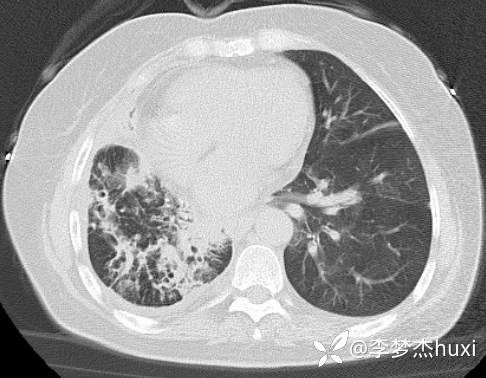

8.22治疗后的胸部CT: